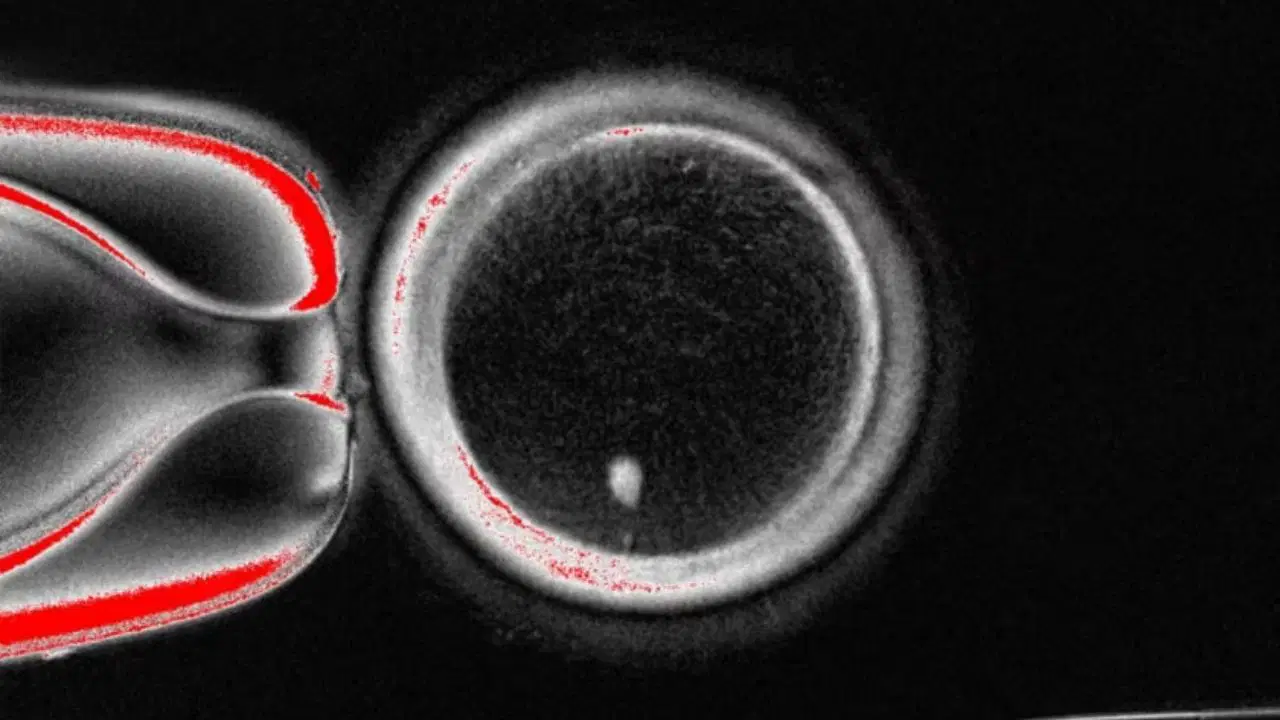

Kısırlık tedavisinde tarihi adım: Deri hücresinden yumurta üretilmeye başlandı